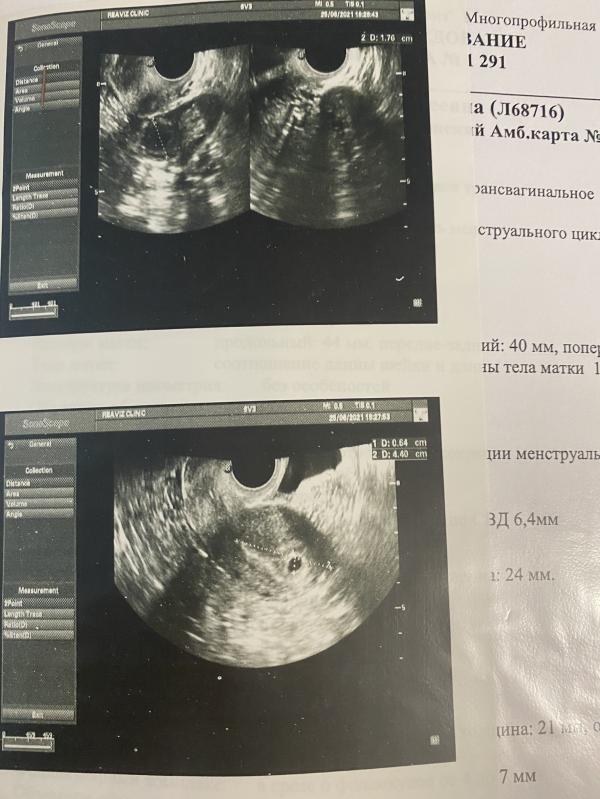

📆1-ый день последних мес - 22.05.21

📺 Первое узи - 25.06.21, срок 5 недель💙